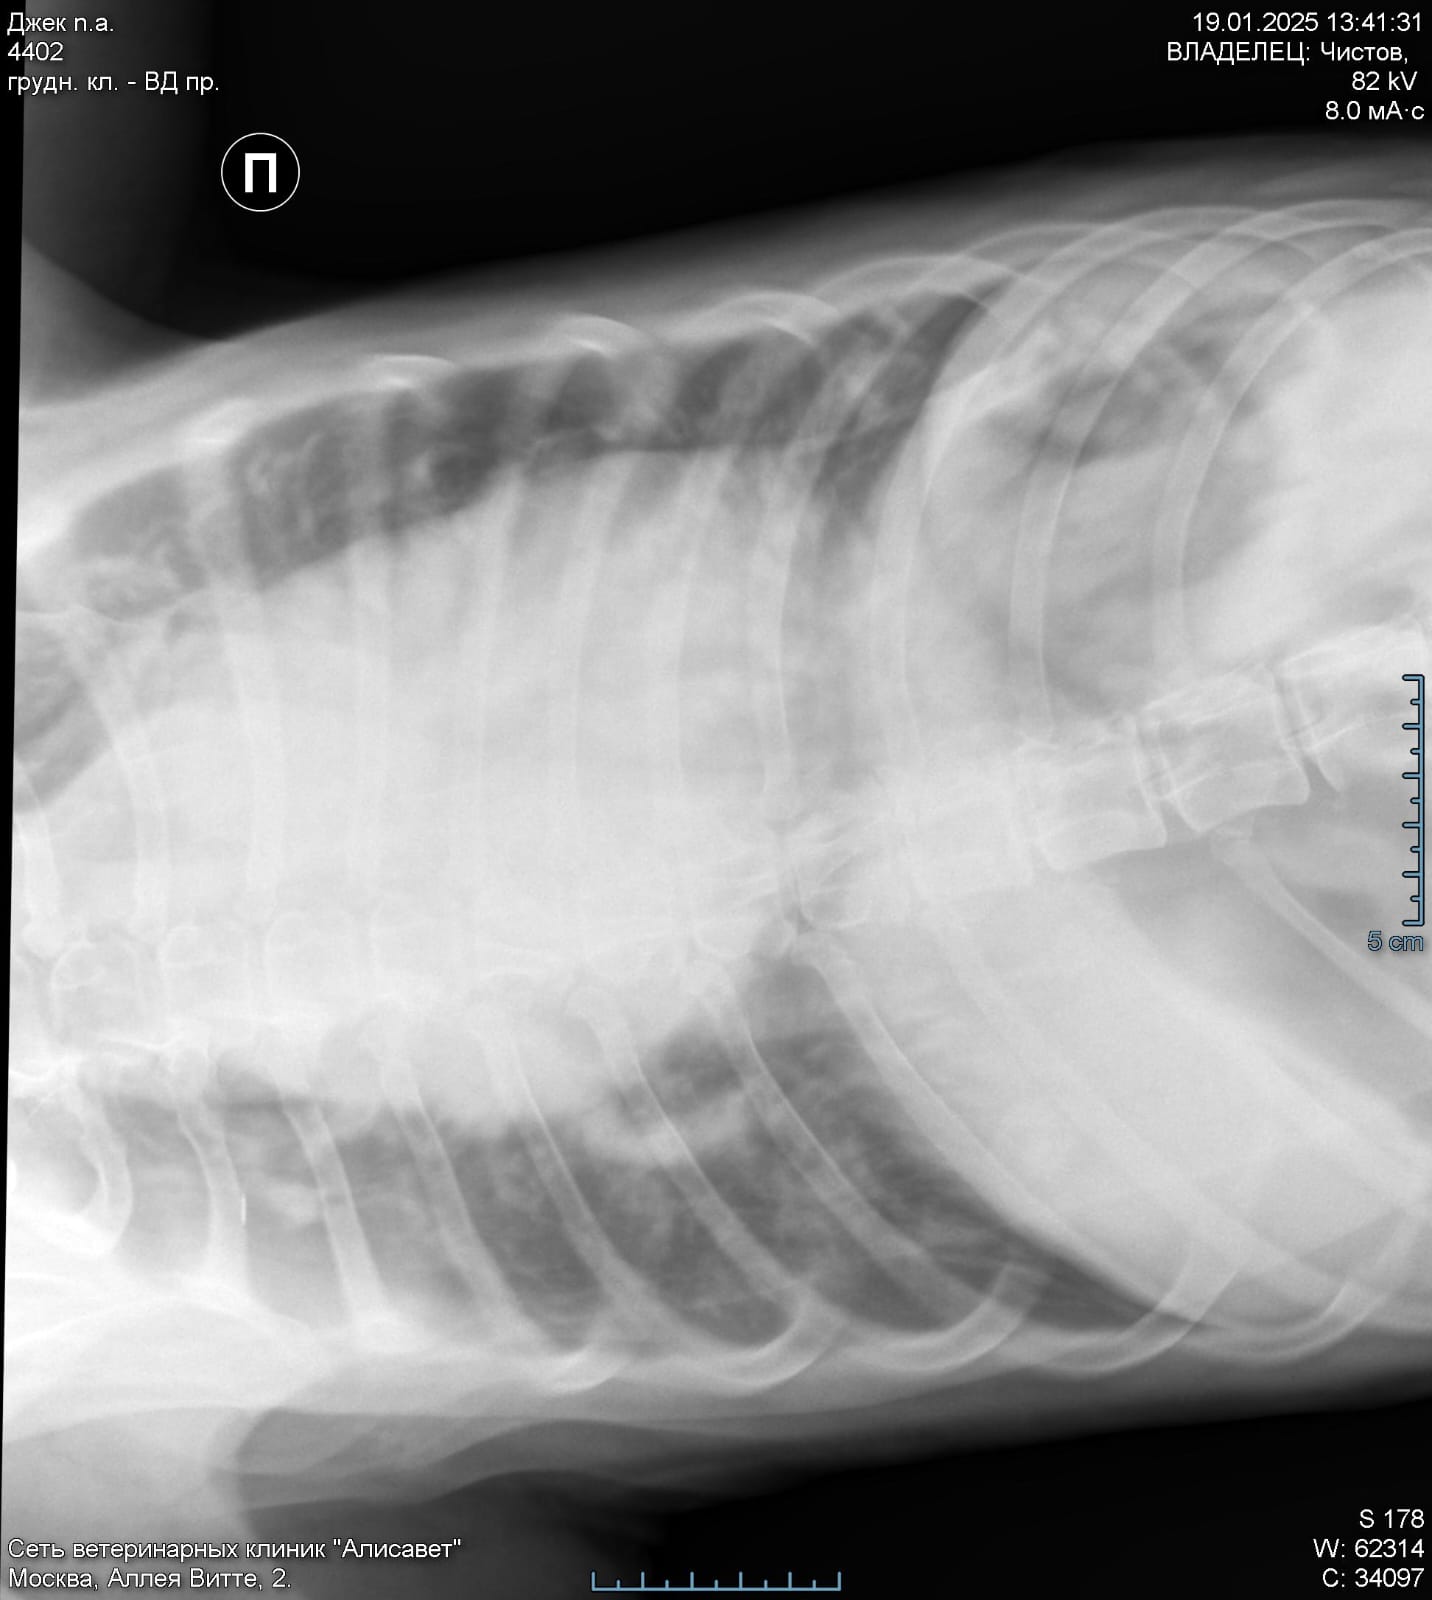

По сердцу и легким отводов нет